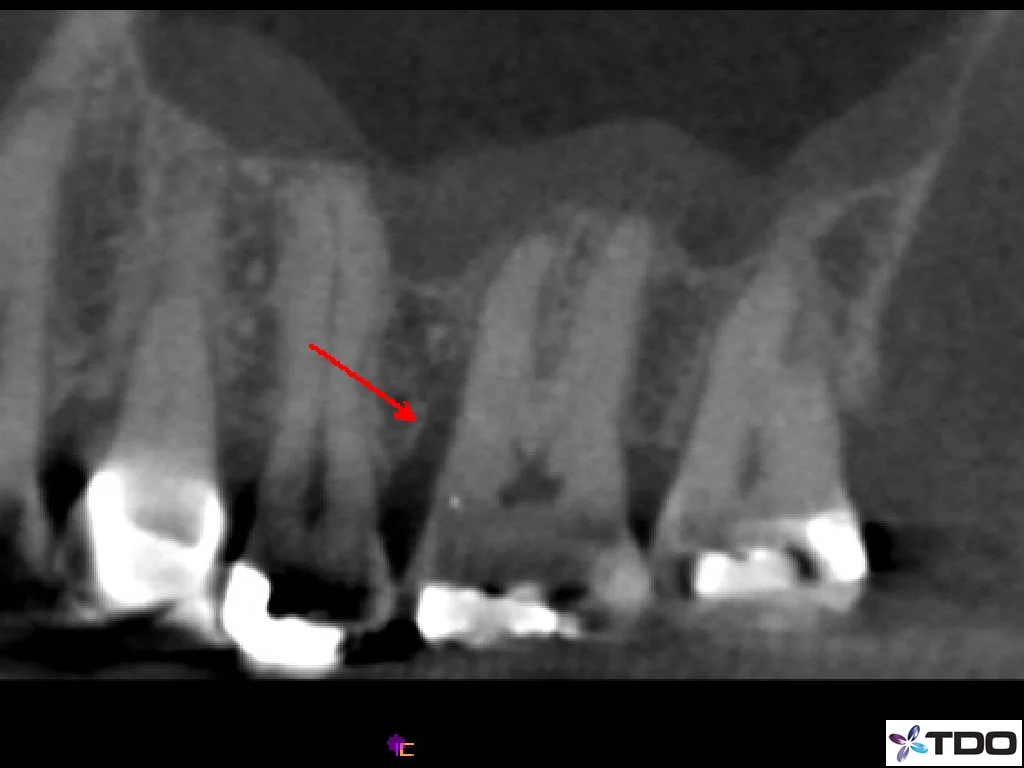

The patient presented without pain for evaluation of persistent sinus tract on the buccal gingiva between teeth #13 and #14. The clinical exam revealed no pain to percussion or palpation. No probing depths were noted upon initial inspection. The CBCT clearly identified tooth #14, and specifically the MB root, as the source of the problem. The tooth was probed again with local anesthesia, and an 8mm narrow pocket was identified on the buccal of the MB root #14. The patient chose to have the tooth extracted since the findings were highly suggestive of a root fracture, and the overall prognosis was guarded to poor.

CBCT Sagittal View